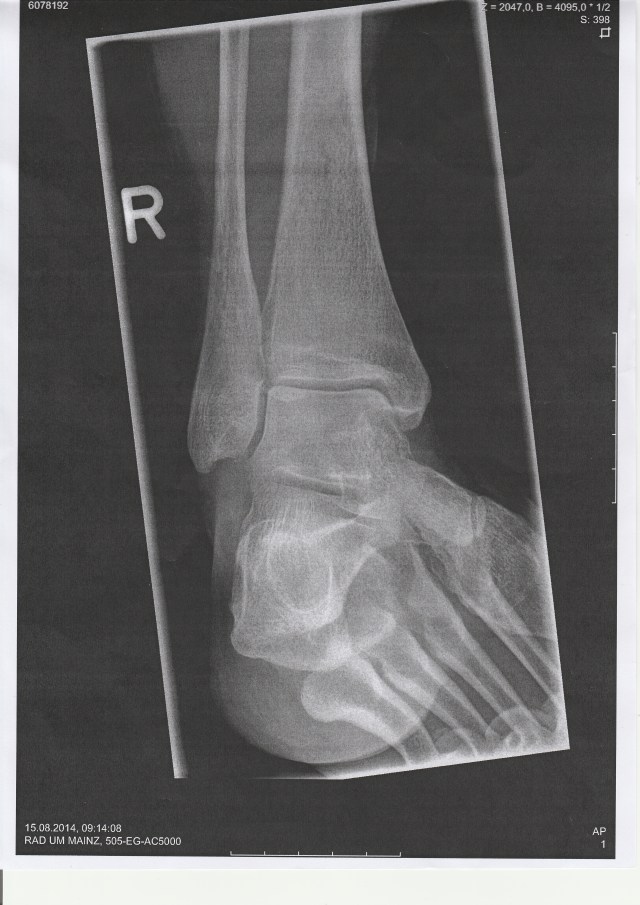

X-rays, back to the doctor who diagnoses a Weber Type A fracture of the ankle in 2 places, here are some crutches (copayment: €5), don’t put any weight on it for 2 weeks, light weight for 2 weeks and then start learning to walk again, here are 3 anticoagulant injections to tide you over the weekend, go and see your GP on Monday, have some thrombosis blood tests, get an appointment with an orthopaedic consultant and in the meantime elevate, rest and cool.